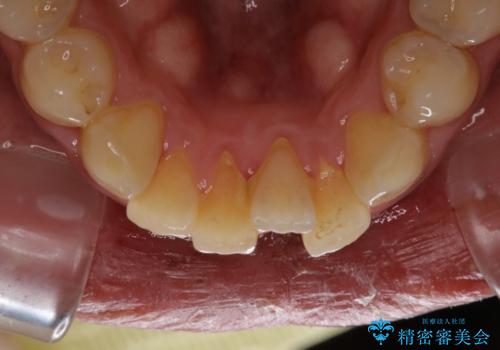

- 結婚式を控えているため、クリーニング希望とのことで来院されました。歯科医院がかなり久しぶりとのことでした。

全体の染め出しを行い、歯科衛生士による専門的自費クリーニング(PMTC)60分コースを行いました。